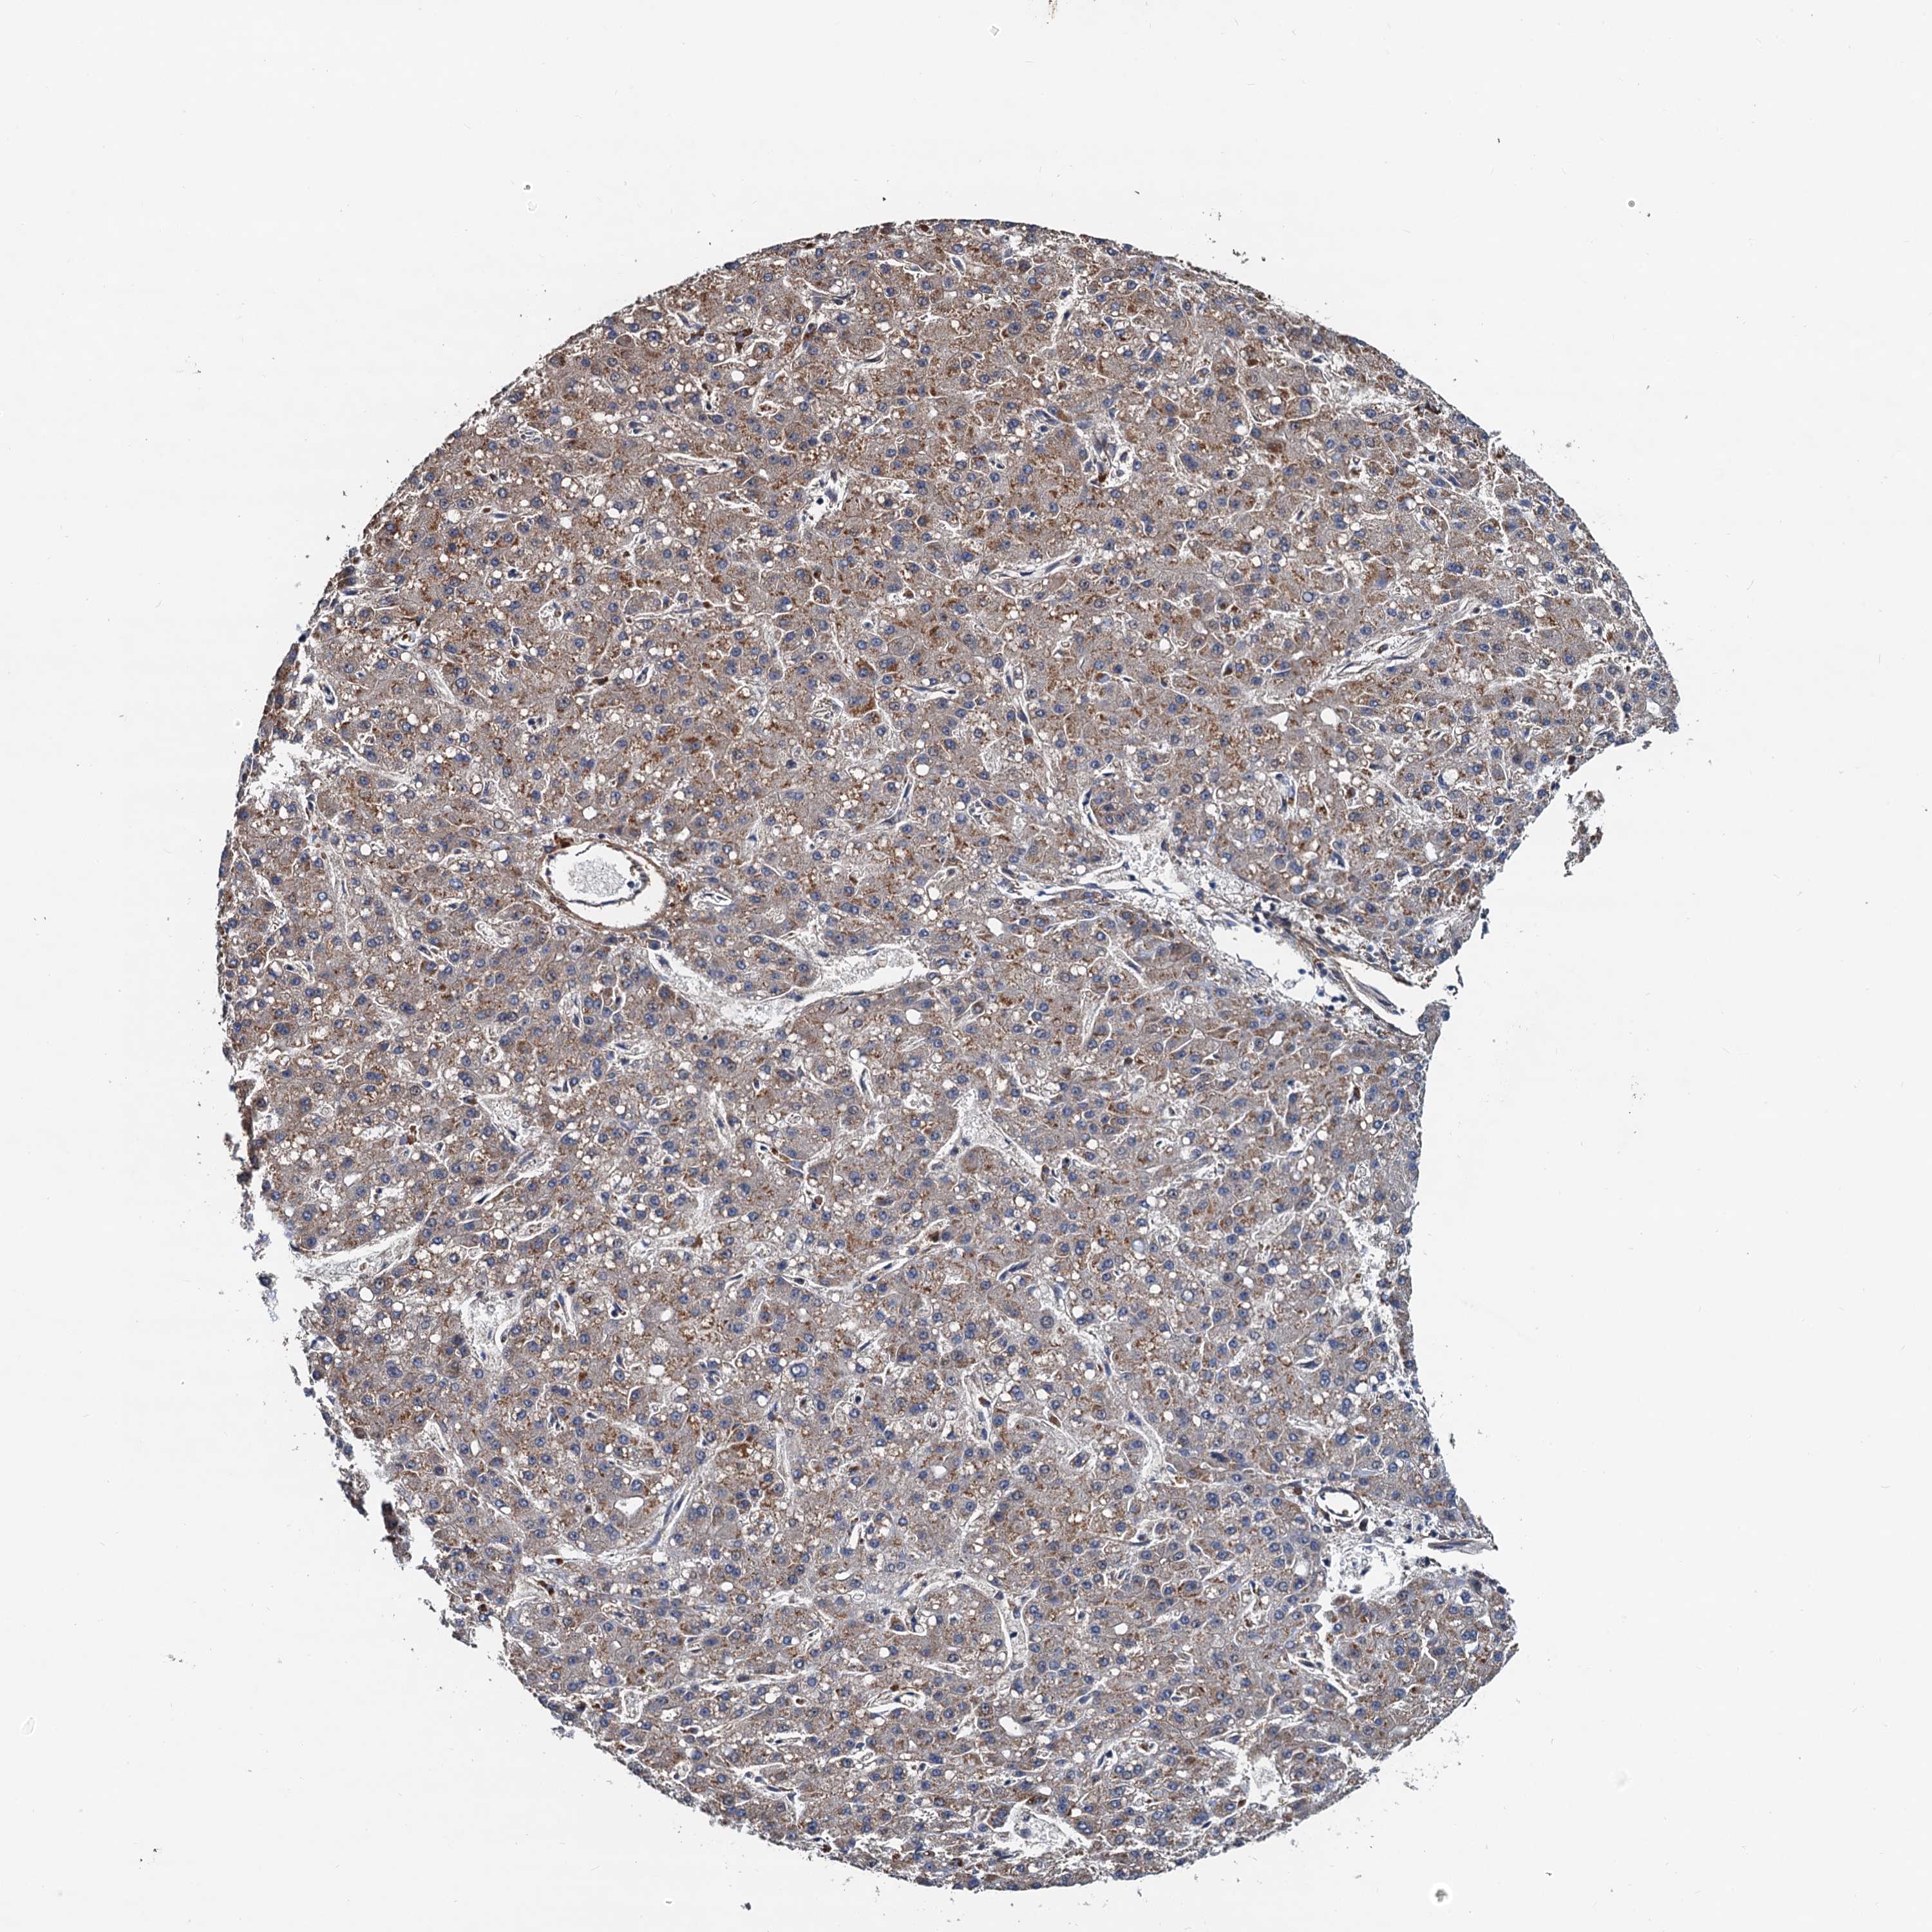

LIVER CANCER - Protein expressioni

A mouse-over function shows sample information and annotation data. Click on an image to view it in a full screen mode. Samples can be filtered based on level of antibody staining by selecting one or several of the following categories: high, medium, low and not detected. The assay and annotation is described here.

Note that samples used for immunohistochemistry by the Human Protein Atlas do not correspond to samples in the TCGA dataset.

Antibody stainingi

Antibody staining in the annotated cell types in the current human tissue is reported as not detected, low, medium, or high, based on conventional immunohistochemistry profiling in selected tissues. This score is based on the combination of the staining intensity and fraction of stained cells.

Each image is clickable and will lead to virtual microscopy that enables deeper exploration of all samples and also displays staining intensity scores, fraction scores and subcellular localization as well as patient and tissue information for each sample.

Antibody HPA039371

Antibody HPA040174

Staining

High

Medium

Low

Not detected

Intensity

Strong

Moderate

Weak

Negative

Quantity

>75%

75%-25%

<25%

None

Location

Nuclear

Cytoplasmic/membranous

Cytoplasmic/membranous,nuclear

Cholangiocarcinoma

Carcinoma, Hepatocellular, NOS